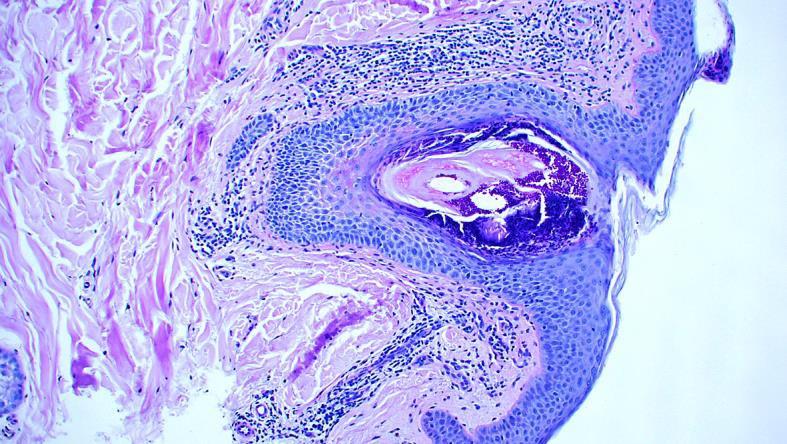

A report on a 40-year-old patient with recalcitrant, suppurative folliculitis is presented. After years of unsuccessful treatment with conventional therapies, the patient was diagnosed with adrenal insufficiency with a low level of circulating cortisol. A few weeks after the patient was subjected to substitution therapy with hydrocortisone, his folliculitis resolved. We discuss the role of plasma cortisol level in the pathogenesis of folliculitis.

本文报告了一名40岁患有顽固性化脓性毛囊炎的患者。在接受多年传统治疗但未成功后,该患者被诊断为肾上腺功能不全,循环皮质醇水平较低。在患者接受氢化可的松替代治疗几周后,其毛囊炎得到缓解。我们讨论了血浆皮质醇水平在毛囊炎发病机制中的作用。